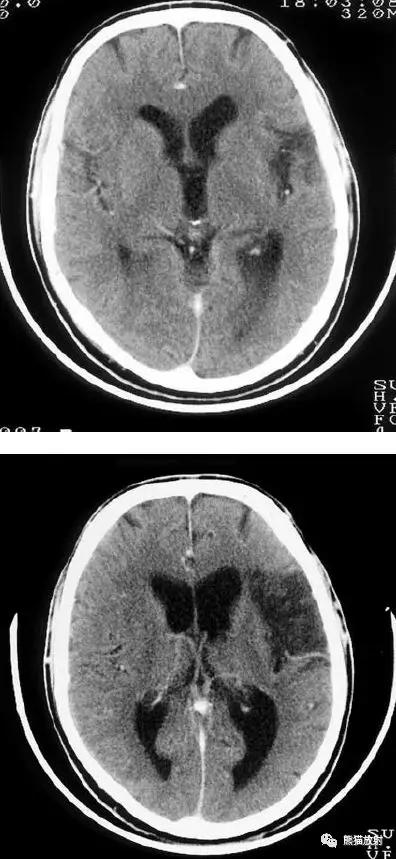

右侧大脑中动脉区域梗死的典型演变:

a)急性期

b)早期亚急性期(2天,从临床起病开始)

c)亚急性晚期(2周后)

d)慢性期(一年后)